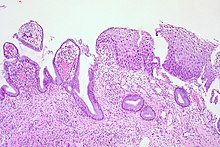

CIN is classified in grades:[17]

| Histology grade | Corresponding cytology | Description | Image |

| CIN 2/3 | High-grade squamous intraepithelial lesion (HSIL) |

|

| CIN 2 (Grade II) |

![]() | |

| CIN 3 (Grade III) |

![]() |